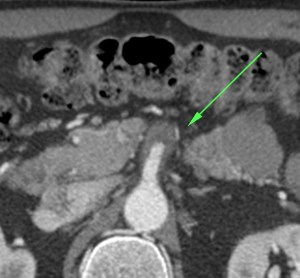

Se realiza TC de abdomen en vacío y con contraste en fase portal:

Estamos ante un cuadro de isquemia intestinal en un paciente con bajo gasto cardiaco con afectación principal de asas intestino delgado, territorio vacularizado por la arteria mesentérica superior.

Flecha roja: colateral que repermeabiliza la AMS.